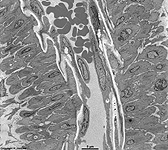

longitudinal section of a

monkey pancreas capillary

Endothelial cells (Terminologia histologica: Endotheliocyti) are cells that cover blood vessels. They are flat, squamous cells with few exceptions (high endothelial cells of venols of lymphatic organs e.g., lymph nodes but not the spleen). In arteries and arteriols they artificially appear columnar in normal preparations due to the fact that the high blood pressure typical for these vessels is no longer present when animals are sacrificed. In consequence the large elastic membranes of these vessels contract and press the endothelial cells up. Fenestrated endothelial cells ((Terminologia histologica: Endotheliocyti fenestrati) are exclusively encountered in capillaries. They show holes (= pores; Terminologia histologica: Fenestrae endotheliocyti, diameter 70 - 100 nm) whereas the non-fenestrated endothelial cells (Terminologia histologica: Endotheliocyti non fenestrati), effect a continious coverage of the vascular lumen. The fenestrae are open and very wide in sinusoids which also lack a basal lamina (sinusoids of liver and spleen). Other fenestrated endothelial cells with open fenestrae are present in the kidney. Other fenestrae are covered by ~ 4 nm thin proteinaceous membranes e.g., thyroid gland. Weibel-Pallade bodies (multitubular bodies; Terminologia histologica: Corpora multitubularia) are sometimes encountered in human endothelial cells. They lack in other species and resemble very tiny tubular mitochondria with a very dark matrix. There is an intake of substances via formation of caveols in non-fenestrated endothelial cells. The resulting small vesicles are transported over a short distance through the cytoplasm to be released on the opposite cell membrane. This transport is called cytopempsis or transcytosis and is best visible in capillary endothelial cells of heart or skeletal muscles.

Whereas endothelial cells of the aorta are somewhat polygonal the following smaller arteries mainly show elongate endothelial cells with a thickness of 2 to 4,5 µm in the nuclear area whereas their peripheral diameters are 0.25 - 1 µm. Widths of 10 to 20 µm and lengths of 20 - 40 µm are typical for arteries. The elongate shape of the cells is caused by the shearing stress of the blood stream. The surface of arterial endothelial cells is about 300 - 800 µm². The cytoplasm or arterial endothelial cells is of moderate electron density and contains contractile stress fibres which are rich in actin filaments and in about parallel orientation to the blood stream whereas endothelial cells of veins hardly show any stress fibres.